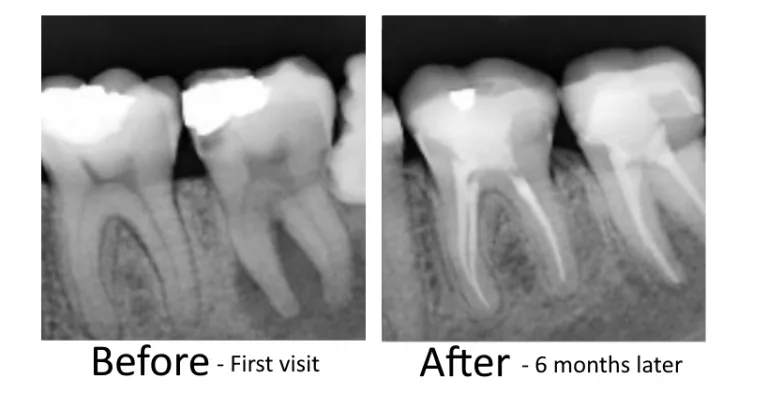

Dr. G Dental Studio is proud to welcome patients from Doral, FL. Our Miami office offers a full range of services for Doral residents — including cosmetic dentistry, dental implants, porcelain veneers, root canals, braces, wisdom tooth removal, and 3D CBCT imaging. Conveniently located just a short drive from Doral with easy parking and flexible appointment times. Call (305) 217-6453 to schedule your visit.